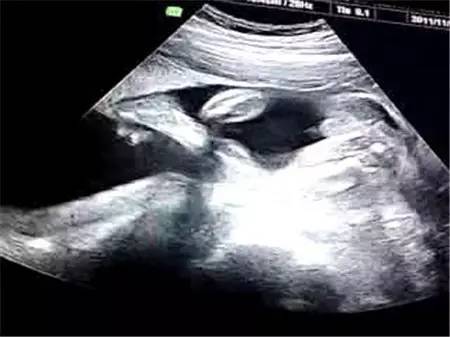

目前世界上最先进的彩色超声设备就是四维彩超。对于孕妇检查来说,这种检查十分准确,而且可以通过各种角度来查看肚子中的宝宝。

我们可以通过四维彩超,清楚的看到宝宝性别。但是我国的法律明令禁止对胎儿性别进行鉴定,所以医生并不会准确告诉你胎儿性别,但是我们可以通过四维彩超的结果来查看宝宝的性别。

从彩超看生男生女?我国严禁查看胎儿性别,医生通过任何途径向孕妇透露或者暗示胎儿的性将会受到法律的追究。所以在做四维彩超时,医生一般会避开胎儿的下半身,不会在图像上显现出胎儿的生殖器官。而且对于年轻的父母来说,无论男宝宝还是女宝宝都是这个家庭的宝贝,了解胎儿的健康发育情况才是做四维彩超的意义。

第四、从胎儿头脸部看

胎头位于耻骨上,头骨光环光整,脑中线居中,胎儿上唇,鼻骨可预示,生男孩。

47mm,透声性杰出,为男孩。